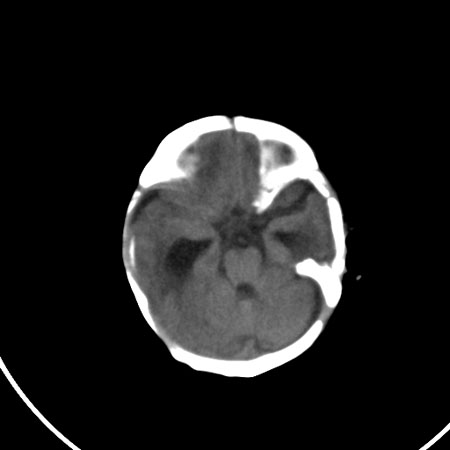

以下是引用小初学者在2009-1-10 17:51:00的发言:[br]考虑缺血缺氧性脑病后遗性改变。

以下是引用拾荒者在2009-1-10 19:23:00的发言:[br]生后有蛛网膜下腔出血病史,现幕上脑室明显扩张,脑室周围白质局限性密度减低,考虑hie脑病后遗表现。